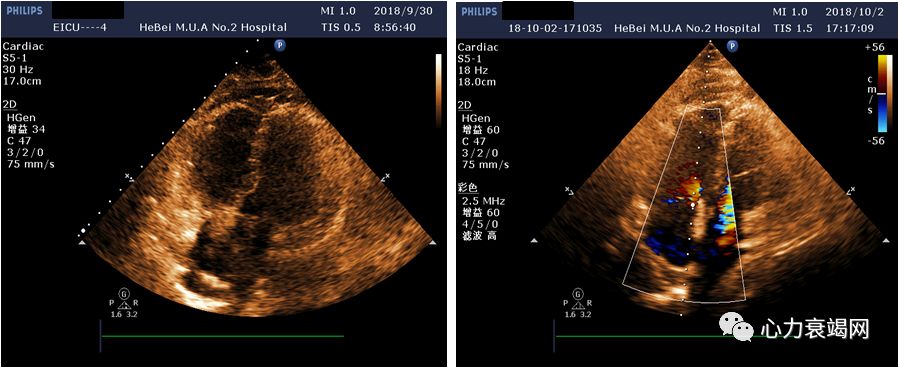

(ECMO第2天,9.30)

心功能较前变化不大

(ECMO第4天,10.2)

心功能较前明显好转,EF50%

➤ 心率120次/分

➤ 血压120/71mmHg

➤ 去甲肾0.2ug/kg/min

➤ SPO2100%